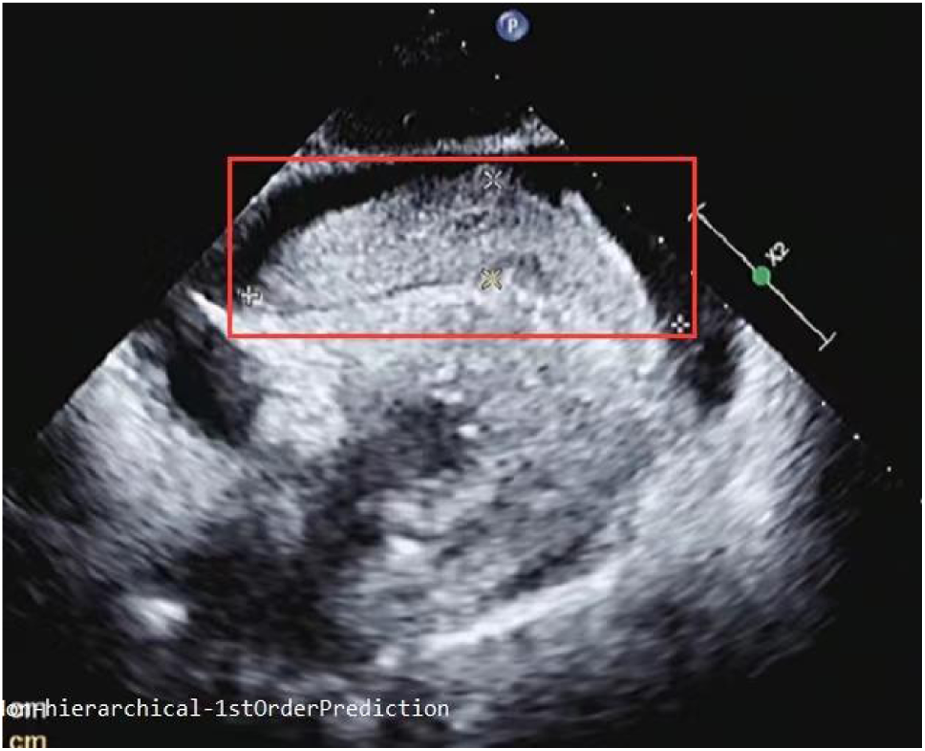

The patient presented with significant subxiphoid pain, dizziness, and nausea upon admission to the ward. Physical examination findings included: temperature of 36.6°C, respiration rate of 25 bpm, blood pressure of 95/65 mmHg, and a heart rate of 82 bpm. The patient was in an irritable state. Moist rales were detected at the bases of both lungs. Cardiac examination revealed weakened heart sounds at the apex, a slightly enlarged cardiac dullness boundary on both sides, a regular heart rhythm, and low heart sounds without murmurs or pericardial friction rub. The abdominal examination was unremarkable. Pulsus paradoxus was not observed. The patient's extremities were cold and clammy. An urgent ECG showed no abnormalities. Color Doppler ultrasound revealed a large mass of soft tissue floating in the pericardial cavity with a low to moderate effusion. There was no abnormal segmental wall motion, and left ventricular systolic function was normal (Figure 2).

Figure 2

Subxiphoid four-chamber view: a giant cord-like soft tissue measuring 93 mm in length and 21 mm in width was observed in front of the right atrium and ventricle.